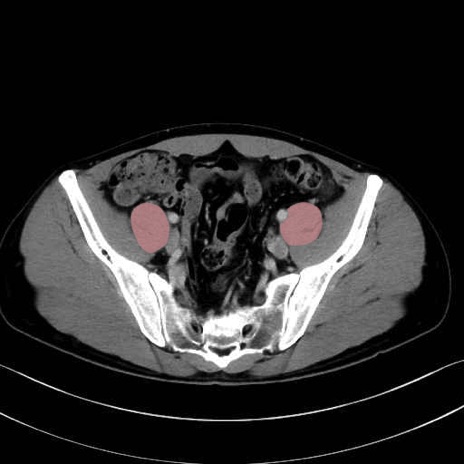

2. 腸腰筋群と骨盤底筋

大腰筋 (Psoas major)

腸骨筋 (Iliacus)